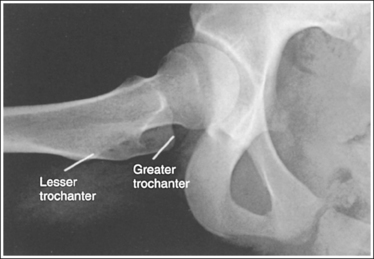

The femoral neck is demonstrated without foreshortening, the greater trochanter is in profile laterally, and the lesser trochanter is superimposed by the femoral neck.

• Accurate leg positioning. To demonstrate an AP hip projection with the femoral neck shown without foreshortening and the greater trochanter in profile, the patient's leg should be internally rotated until the foot is angled 15 to 20 degrees from vertical and the femoral epicondyles are positioned parallel with the imaging table (Figure 7-4; see Figure 7-1). A sandbag or tape may be needed to help the patient maintain this internal leg rotation.

• Poor leg positioning. The relationship of the patient's leg to the imaging table determines how the femoral neck and trochanters are shown on an AP hip projection. In general, when patients are relaxed, their legs and feet are externally (laterally) rotated. On external rotation, the femoral neck declines posteriorly (toward the table) and is foreshortened on an AP hip projection. Increased external rotation increases the degree of posterior decline and foreshortening of the femoral neck on the image. If the patient's leg is externally (laterally) rotated enough to position the foot at a 45-degree angle and an imaginary line connecting the femoral epicondyles at a 60- to 65-degree angle with the imaging table, the femoral neck is demonstrated on end and the lesser trochanter is demonstrated in profile (Figure 7-5; see Image 3). If the patient's leg is positioned with the foot placed vertically and an imaginary line connecting the femoral epicondyles at approximately a 15- to 20-degree angle with the imaging table, the lesser trochanter is demonstrated in partial profile and the femoral neck is only partially foreshortened (see Image 4).

The ischial spine is demonstrated without pelvic brim superimposition, the sacrum and coccyx are not aligned with the symphysis pubis but are rotated away from the affected hip, and the obturator foramen is narrowed. The patient was rotated toward the affected hip. The femoral neck is foreshortened, and the lesser trochanter is demonstrated in profile. The patient's leg was externally rotated.

Rotate the patient away from the affected hip until the ASISs are positioned at equal distances from the imaging table. Internally rotate the patient's leg until the foot is angled 15 to 20 degrees from vertical and the femoral epicondyles are positioned parallel with the imaging table, as shown in Figure 7-4.

The femoral neck is completely foreshortened, and the lesser trochanter is demonstrated in profile. The patient's leg was in external rotation with the foot positioned at a 45-degree angle and the femoral epicondyles at a 25- to 30-degree angle with the imaging table, as shown in Figure 7-5.

Internally rotate the patient's leg until the foot is angled 15 to 20 degrees from vertical and the femoral epicondyles are positioned parallel with the imaging table, as shown in Figure 7-4.

The femoral neck is partially foreshortened, and the lesser trochanter is demonstrated in profile. The patient's leg was externally rotated, bringing the foot vertical and the femoral epicondyles to approximately a 15- to 20-degree angle with the imaging table.